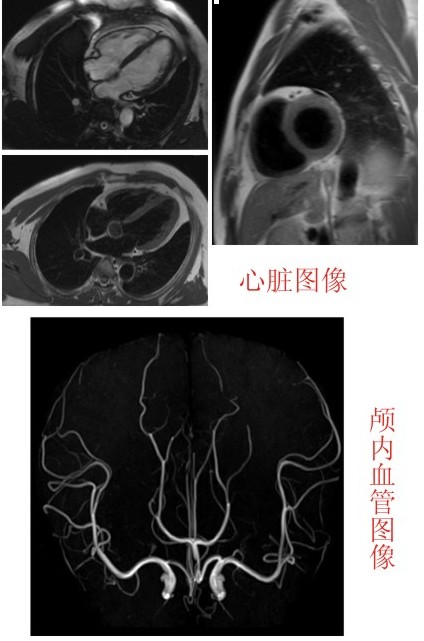

与早期传统磁共振相比,扫描视野更大、扫描速度更快、图像对比度更清晰,能对人体各个部位进行多序列的扫描检查,并可显示任意方位的图像,能开展多项诊疗工作。可应用于全身各部位的常规检查,特别是对脑、脊髓、骨关节软组织神经、血管和体部脏器的检查有独到之处。该设备投入使用后,将为神经内科、神经外科、普外科、泌尿外科、骨科、心血管内科、肿瘤科等科室患者提供无辐射、无创伤的影像检查,医生能够从其高质量的图片清楚地看到许多以前无法看清的细小病灶,发现以前无法发现的疾病,为疾病的准确定性提供了保证,对临床具有极高的指导价值。

该机可进行神经系统、心血管系统、骨关节系统等全身各个系统的不同疾病的检查,对血管梗塞、血管瘤、动脉夹层、血管畸形、胆道以及泌尿系结石、肿瘤、梗阻的诊断具有极大的临床价值,可发现CT无法发现的超早期脑梗塞病变,为挽救患者生命和改善预后、减少致残率赢得时间。